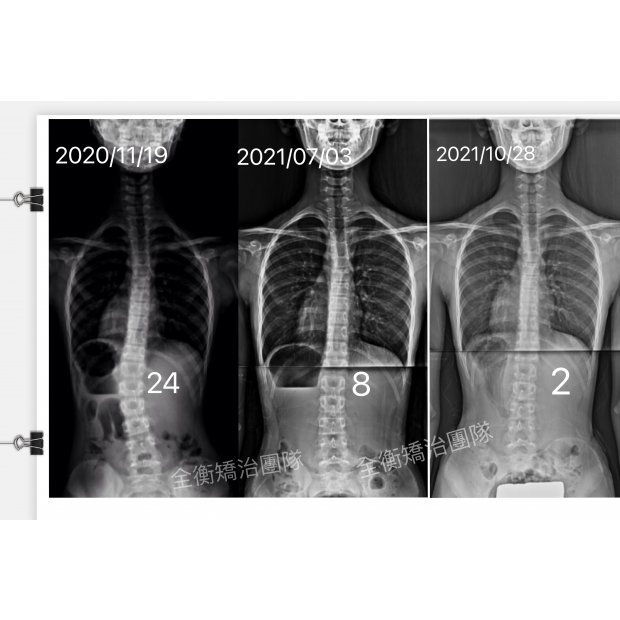

11歲24度側彎女孩,把握脊椎側彎黃金矯正期,收穫驚喜連連11歲24度側彎女孩,把握脊椎側彎黃金矯正期,收穫驚喜連連

11歲24度側彎女孩

治療一年後脊椎幾乎變直

24°→8°→2°